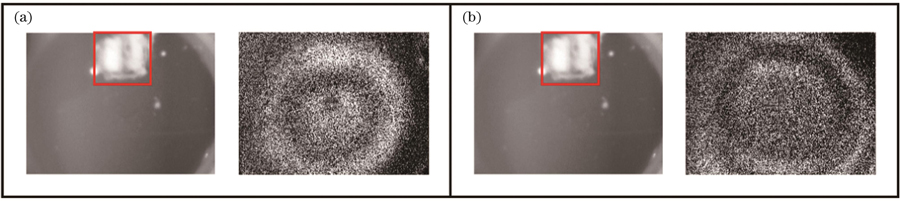

在钙化薄膜的实验验证中,为了模拟真实的耳膜钙化情况,在薄膜表面涂抹不同厚度的尺寸为3 mm×3 mm的钙化材料。分别在相同位置处涂抹0.1 mm和0.3 mm厚度的钙化材料,如

图 13. 钙化薄膜的一阶振动模态图。(a)钙化厚度为0.1 mm的薄膜;(b)钙化厚度为0.3 mm的薄膜

Fig. 13. First-order vibrational mode diagrams of calcified films. (a) Film with calcification thickness of 0.1 mm; (b) film with calcification thickness of 0.3 mm